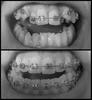

Прошло уже три недели. Я уже практически привыкла к брекетам, и, несмотря на разодранную изнутри левую щеку (и сверху, и снизу), я их уже практически люблю =))) причем, мне кажется, глядя в зеркало, что зубы прям подвинулись. Однако, по фото такого сказать не могу:

braces020413.jpg

По фото ощущение, что передние зубы разъезжаются =( не хотелось бы, конечно. Читать далее »